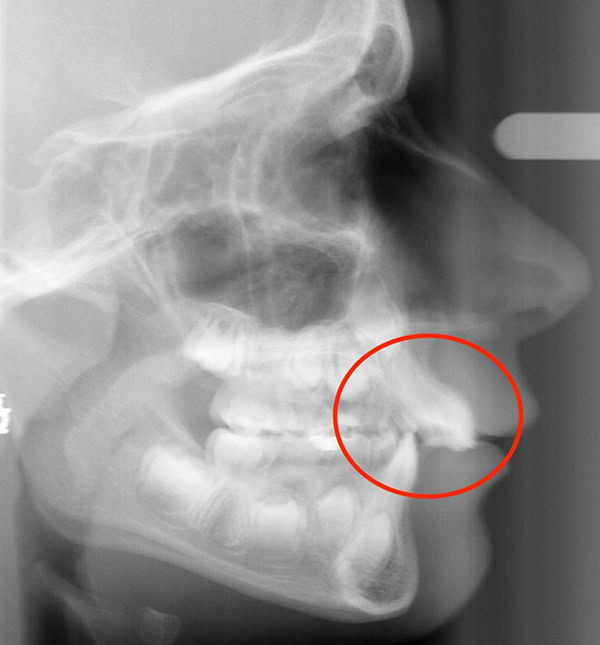

Actual Patient: Alexander

Before

After

Before

After

Severe “Underbite”, Narrow Jaws, Adult Teeth Not Growing In

Front View

Top View

Right & Left Sides